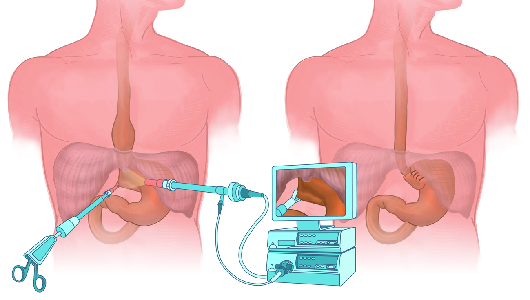

Detailreiche Fotografien aus der medizinischen Praxis ergänzen die Texte; moderne, genaue,

wissenschaftliche Zeichnungen geben Einblick in die Anatomie und die Funktion der Lunge und

anderer Organe.